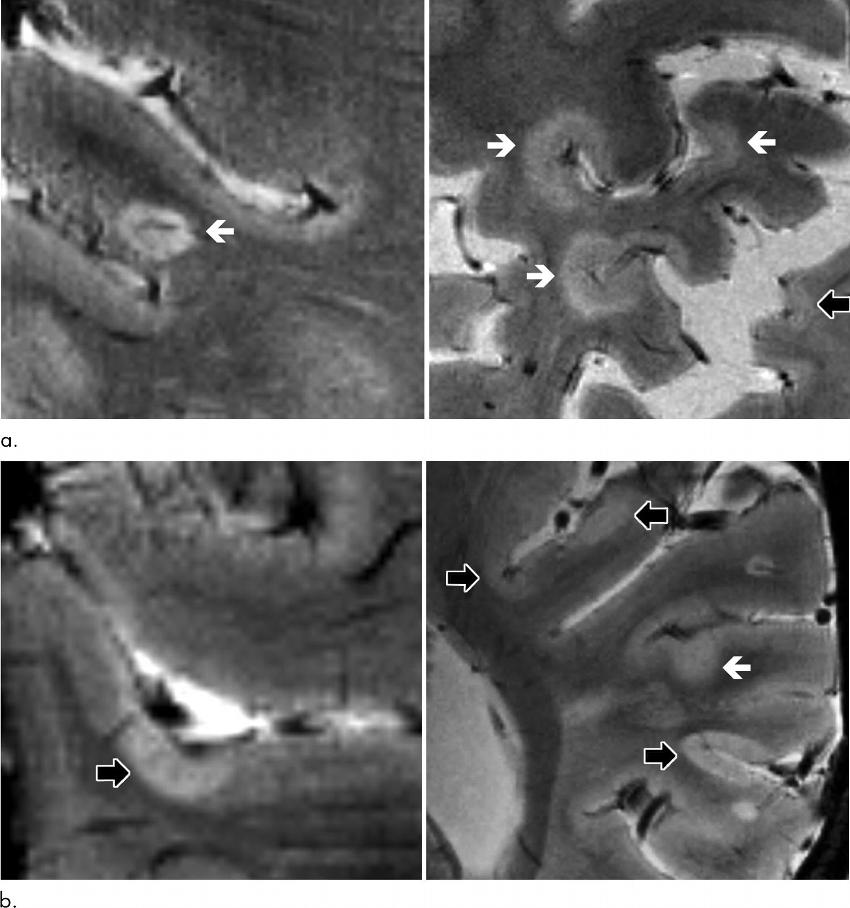

Figure 2. Axial 7.0-T T2*-weighted images show examples of leukocortical lesions (white arrows) and intracortical lesions (black arrows) along with juxtacortical and periventricular white matter lesions in different patients with multiple sclerosis (MS). (a) Images of two different brain locations in a 59-year-old man with secondary progressive MS (SPMS). (b) Images of two different brain locations in a 40-year-old woman with SPMS.